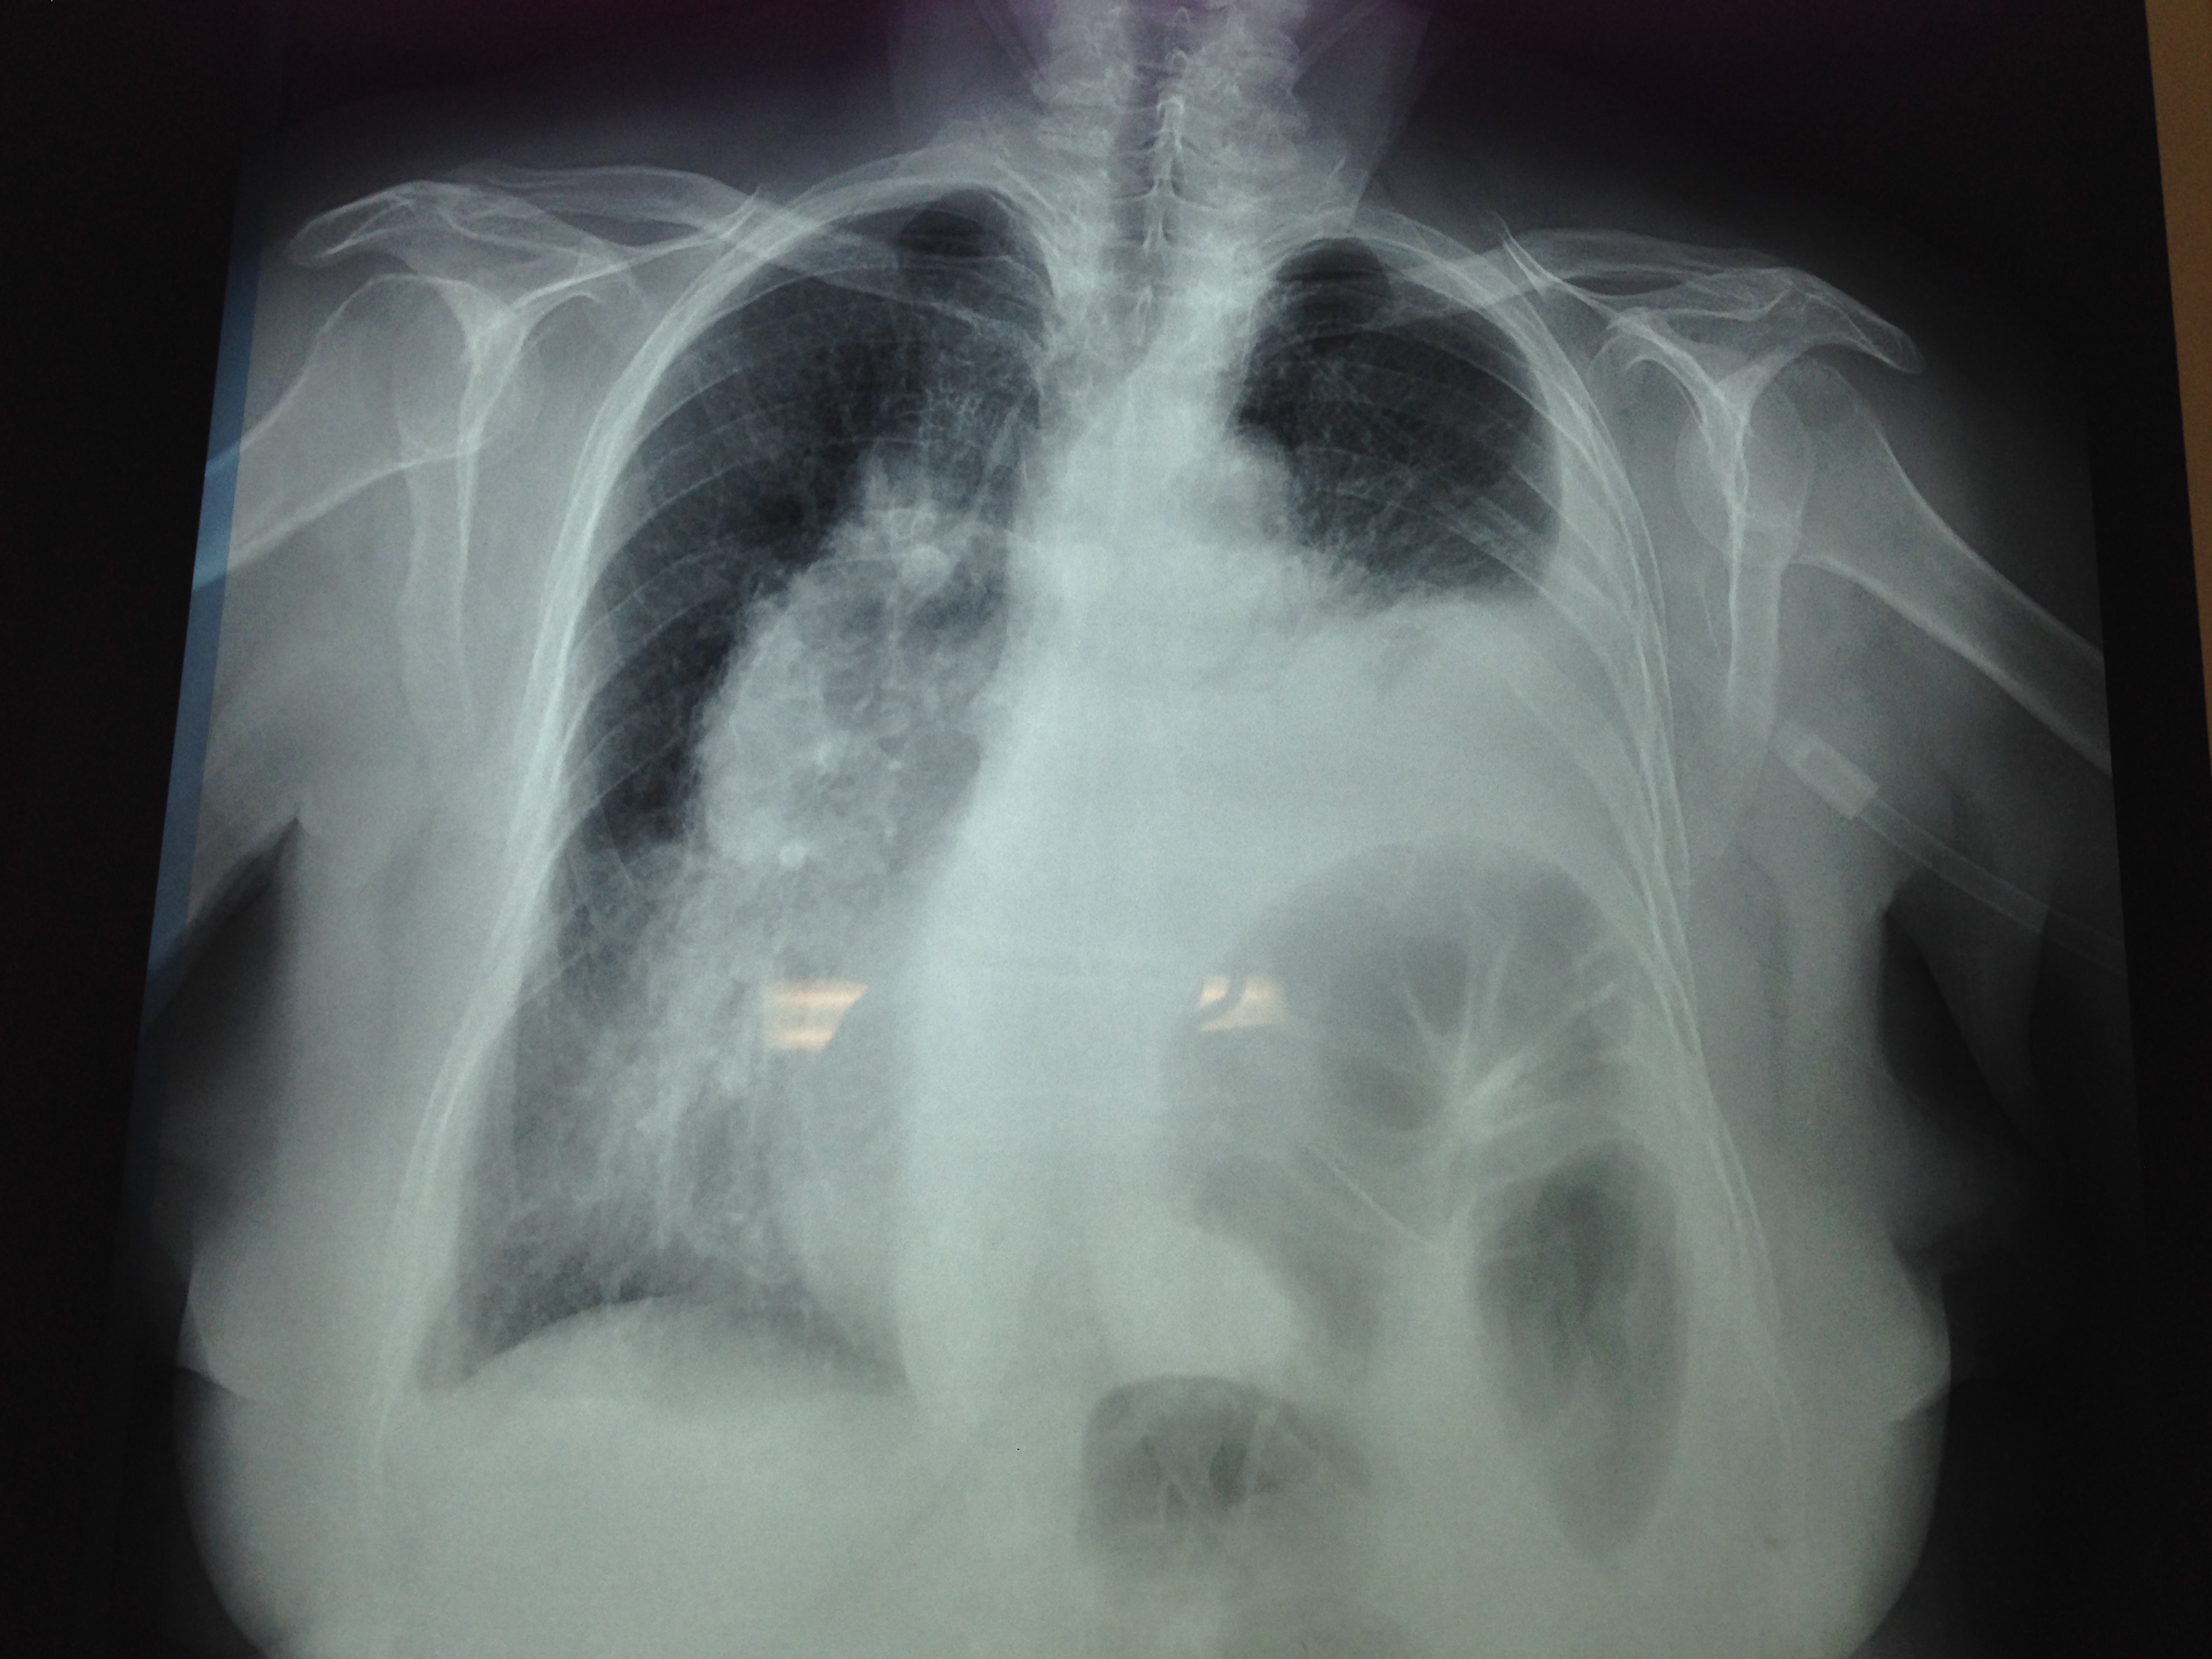

Ακτινογραφία θώρακος μετά από πλύχυνση του αριστερού διαφράγματος. Η πλήρης έκπτυξη του αριστερού πνεύμονα είναι εμφανής. Το αριστερό διάφραγμα πλέον φαίνεται ισιωμένο σε φυσιολογική θέση (Ευγενική παραχώρηση Dr. V. Penopoulos)